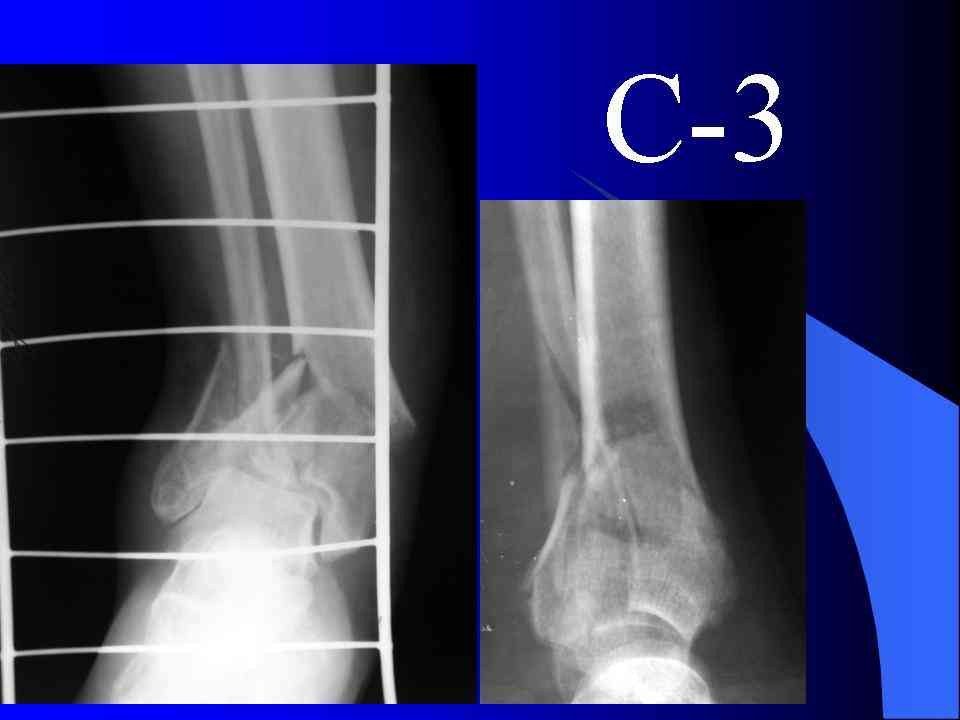

На рентгенограммах типичный перелом пилона по типу С-3. есть опыт до 100 открытых опреаций у нас в клинике. 20 примерно в год. Принцип один -все внутрисуставные переломы нуждаются в открытой репозиции и внутренней стабильной фиксации. При поступлении КТ не надо, так как получается только нагромождение костей. Истинной картины нет. Главное восстановить длину малоберцовой кости - это ключ к успеху. При поступлении меньше всего надо думать о сосудистых расстройствах, т.к. сама операция и репозиция даже сначала частичная даёт улучшение сосудитых нарушений. Причём очень быстро. Операция в 2этапа. При поступлении доступ позади наружной лодыжки, причём обязательно. После этого репозиция малоберцовой кости и фиксация пластиной 1/3 трубки под винт 3,5. Дренаж и любой аппарат наружной фиксации. Затем после спадения отёка на 5-7-10 день аппрат снимается и дугообразный разрез спереди от медиальной лодыжки 10-12 см. Главной чтобы расстояние между 1 и вторым разрезом было не меньше 7-8 см. Тогда не будет некрозов лоскутов. Таранная кость используется как матрица на неё укладываются отломки и фиксируются пицами. Ренг-контроль. Отломки лежат все отдельно, но ничего не высыпется. При переломах С-3 всегда нужна костная пластика (из крыла). Фиксация пластиной лист клевера простой или LCP. Гипс не нужен. Дренаж до 48 часов. Операция длится 3-4 часа обязательно без жгута. Посылаю примерно такой же случай.

Спасибо за убедительную и оптимистичную презентацию. двухэтапная стабилизация и реконструкция С3 тиб. пилона с ранней мобилизацией сустава оправдана практическим опытом и признана оптимальной тактикой ведения

больных с этим типом повреждения. К сожалению, следует признать, что далеко не всегда удается восстановить абсолютную конгруэнтность суставной

поверхности б\б кости, поэтому отдалённая функциональная перспектива такого сустава неопределённа. Но на сегодня ничего лучшего пока не придумано и чем чаще этот подход будет применяться, тем меньше проблем возникнет у больных, лечённых альтернативными методами. Согласен с вами, что стоит пытаться